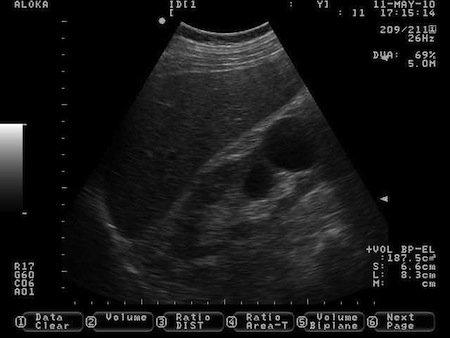

Fot. Przykładowy skan USG przedstawiający nerkę prawą z torbielą dolnego bieguna średnicy około 2,5 cm.

Mam 55 lat i od jakiegoś czasu nieustannie bolą mnie plecy w okolicy lędźwiowej. Zrobiłam sobie prywatnie USG brzucha żeby ocenić nerki. W opisie radiolog napisał : obie nerki położone typowo, bez zastoju i ech złogów z dobrze zachowaną warstwą miąższową. W dolnym biegunie nerki prawej torbiel korowa średnicy około 2,5 cm. Czy torbiel w prawej nerce może być przyczyną moich dolegliwości?